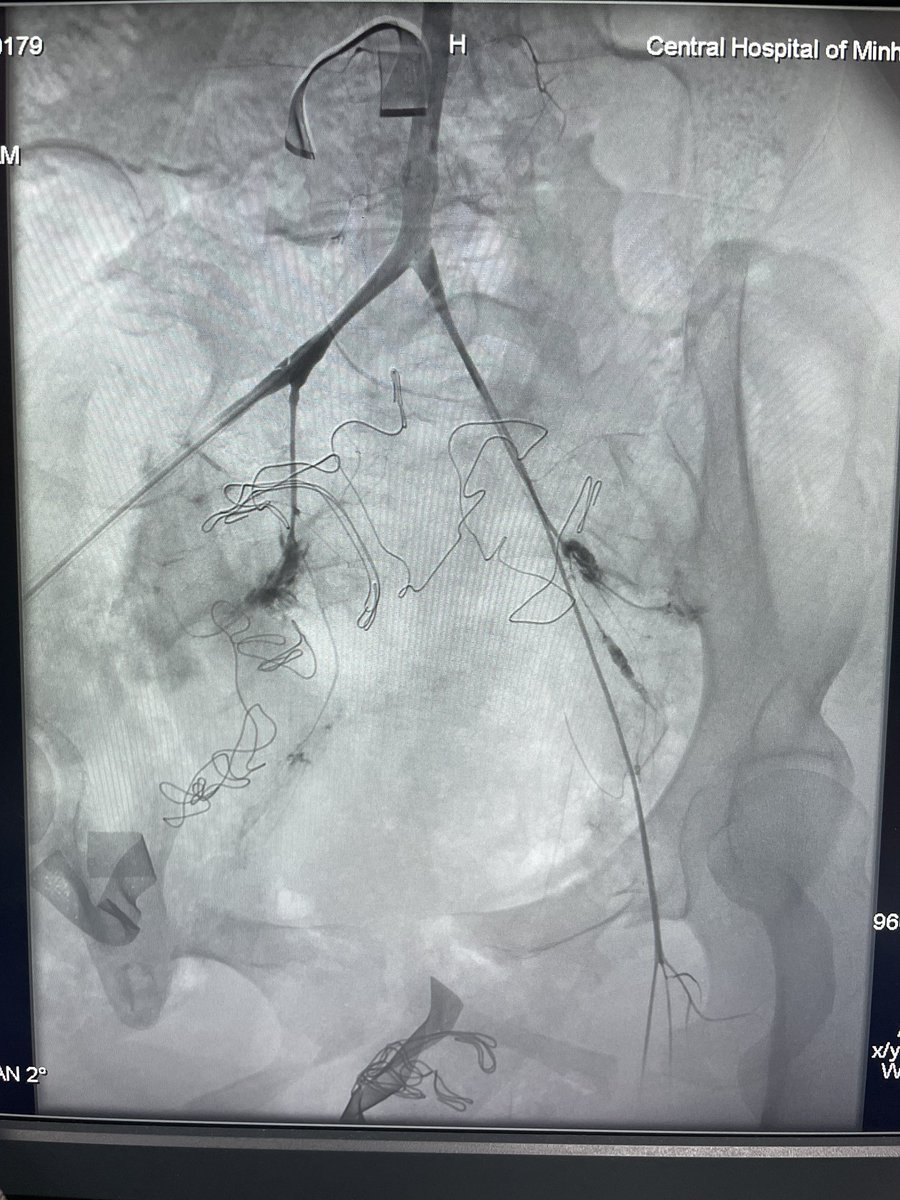

45y male CLI with CAD & hx of CABG POBA of rt SFA, retrograde crossing of lt CIA by balloon supported Command 0.018 gw, bilateral kissing bare metal BES Restoration of pedal pulses #vascular Fórum Vascular CLI Global Society #CLIFighter #endovascular

45y male CLI with CAD &amp; hx of CABG

POBA of rt SFA, retrograde crossing of lt CIA by balloon supported Command 0.018 gw, bilateral kissing bare metal BES

Restoration of pedal pulses

#vascular <a href="/VascularForum/">Fórum Vascular</a> <a href="/CLI_Global/">CLI Global Society</a> #CLIFighter #endovascular